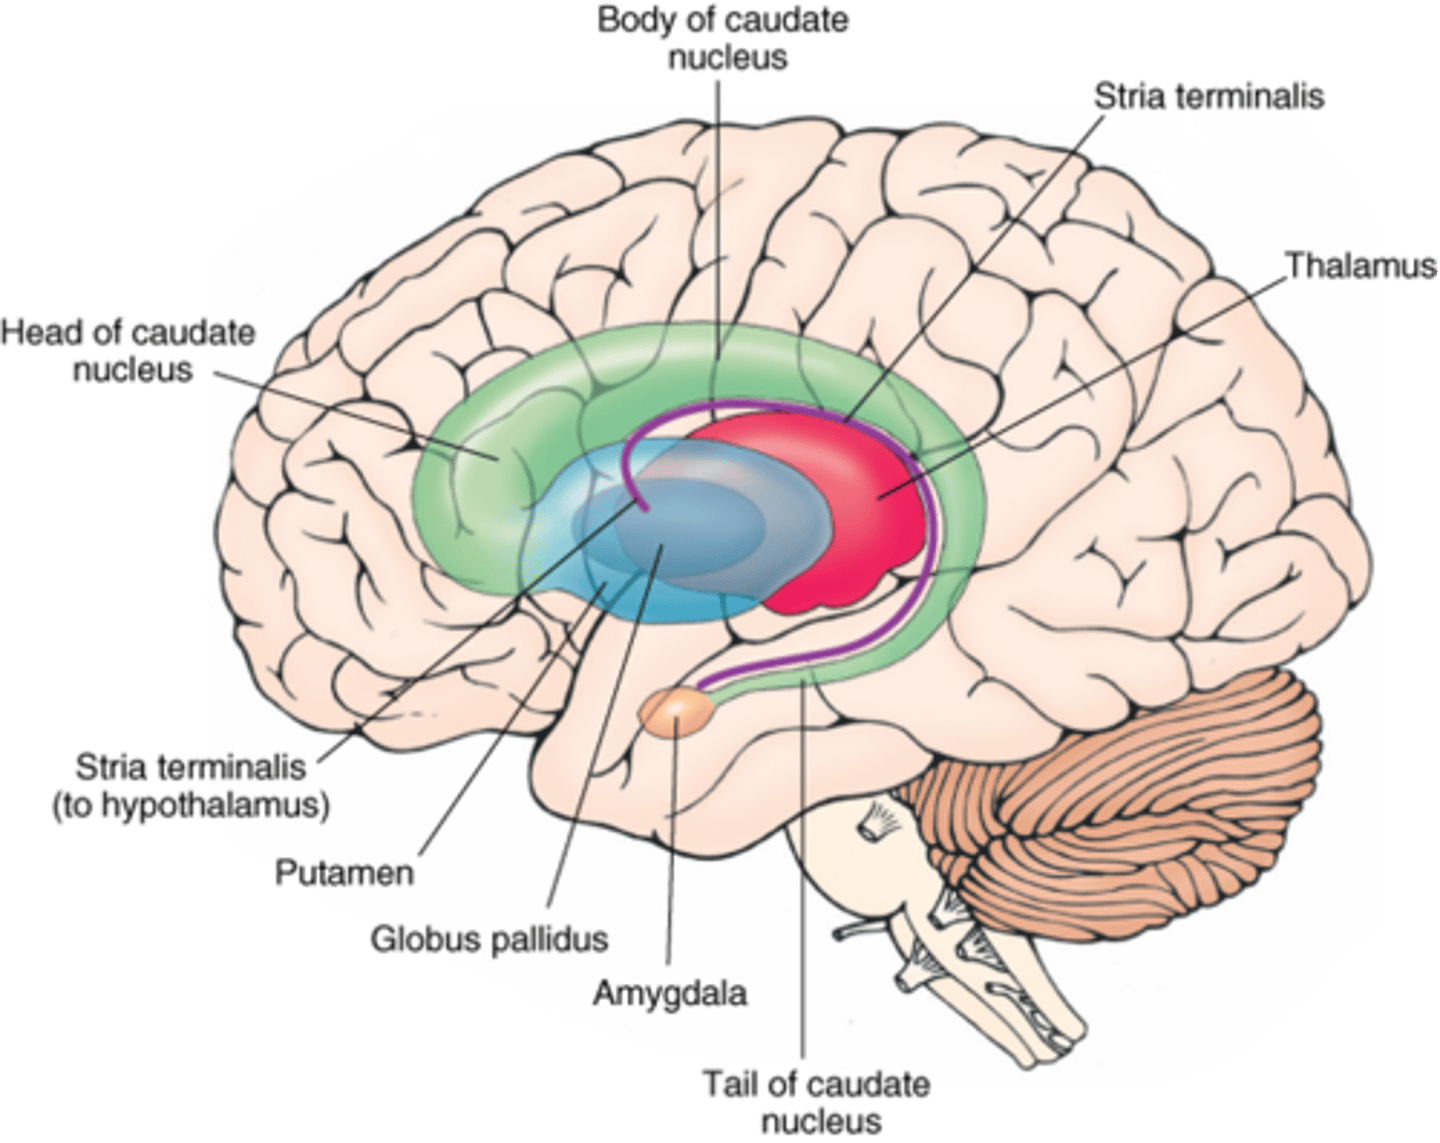

what cerebral gray matter structure is a collection of subcortical nuclei primarily involved in motor control?

basal ganglia

what cerebral gray matter structure has a gate-keeping mechanism for the initiation of motor movement (choosing which actions to allow and which to inhibit)?

basal ganglia

what cerebral gray matter structure has roles in motor learning, executive functions, behaviors, and emotions?

basal ganglia

what are the 3 parts of the basal ganglia? what runs between them?

1. caudate nucleus

2. putamen

3. globus pallidus

internal capsule

what part of the basal ganglia is the C-shaped structure that is most medial?

caudate nucleus

what part of the basal ganglia is medial to the putamen?

globus pallidus

the putamen and globus pallidus of the basal ganglia are collectively called the _______________ nucleus

lentiform